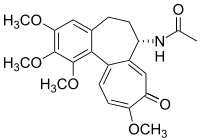

Colchicine alkaloids [144]

|

Tyrosine or phenylalanine → dopamine → autumnaline → colchicine[145] | Colchicine, colchamine[144] | |